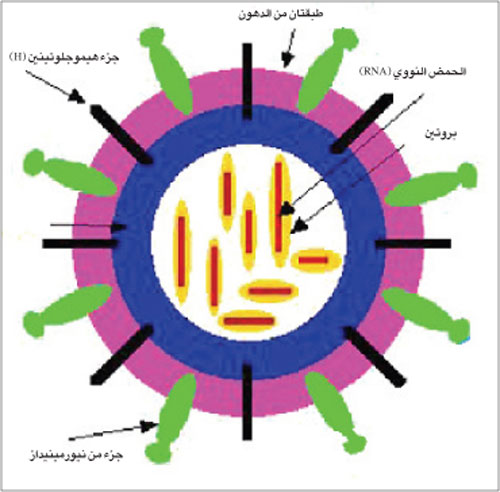

تركيب فيروس

الأنفلونزا

كما اوضحنا تنقسم الانفلونزا الى ثلاثة انواع او مجموعات «A» - «B» - «C» وفقا لنوع الفيروس المسبب لها.

وجميع الفيروسات حاملة للمادة الوراثية «RNA» وهو ما يعرف بالحمض النووي الريبوزي التي تحتوي على ثمانية جينات ويحيط بها غشاء داخلي من البروتين.

كما يحميها من الخارج غلاف يحوي نوعين من الجزئيات البروتينية السطحية وهما:

• جزيء الهيماغلوتينين «Haemagglutinin» ويرمز له بالبروتين «H» والذي يلعب دورا اساسيا في قدرة الفيروس على اصابة خلايا الجهاز التنفسي باندماجه مع مستقبلات موجودة حول الخلية ويتكاثر بداخلها.

• جزيء نيورامينداز «Newraminidase» يرمز له بالبروتين «N» ودوره يتمثل في خروج الفيروسات الوليدة من الجهاز التنفسي لتنتشر في انحاء الجسم.

ويوجد من الجزيء «15H» نوعا ويوجد من الجزيء «N9» وأنواع.

وهناك ثلاثة انواع فقط من الخمسة عشر نوعا من الجزيء «H» خاصة بالانسان (H1 - H2 - H3) ونوعان من الجزيء «N» من التسعة جزيئات «N» وهما (N1 - N2).

تركيب فيروس

الأنفلونزا

كما اوضحنا تنقسم الانفلونزا الى ثلاثة انواع او مجموعات «A» - «B» - «C» وفقا لنوع الفيروس المسبب لها.

وجميع الفيروسات حاملة للمادة الوراثية «RNA» وهو ما يعرف بالحمض النووي الريبوزي التي تحتوي على ثمانية جينات ويحيط بها غشاء داخلي من البروتين.

كما يحميها من الخارج غلاف يحوي نوعين من الجزئيات البروتينية السطحية وهما:

• جزيء الهيماغلوتينين «Haemagglutinin» ويرمز له بالبروتين «H» والذي يلعب دورا اساسيا في قدرة الفيروس على اصابة خلايا الجهاز التنفسي باندماجه مع مستقبلات موجودة حول الخلية ويتكاثر بداخلها.

• جزيء نيورامينداز «Newraminidase» يرمز له بالبروتين «N» ودوره يتمثل في خروج الفيروسات الوليدة من الجهاز التنفسي لتنتشر في انحاء الجسم.

ويوجد من الجزيء «15H» نوعا ويوجد من الجزيء «N9» وأنواع.

وهناك ثلاثة انواع فقط من الخمسة عشر نوعا من الجزيء «H» خاصة بالانسان (H1 - H2 - H3) ونوعان من الجزيء «N» من التسعة جزيئات «N» وهما (N1 - N2).